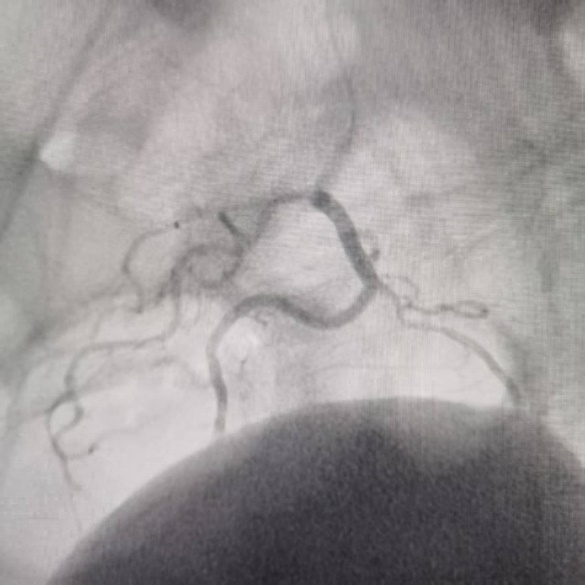

术后造影显示靶血管血流截断,外溢征象完全消失,达到解剖性止血目标。

术后